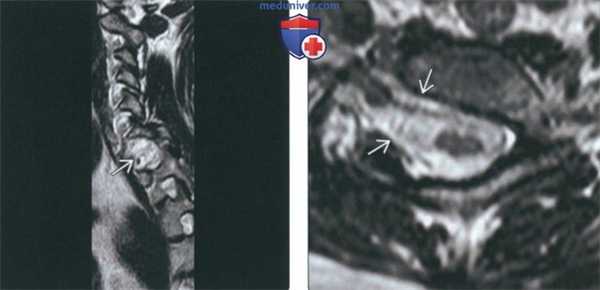

(Слева) На сагиттальной КТ (СКФ) определяется легкое нарушение сегментации на одном уровне (С4-С5). Узкая «талия» рудиментарного диска и слияние остистых отростков типичны для этой патологии.

(Справа) На корональной КТ в костном окне определяется вариант нарушения сегментации в виде крупной, хорошо отграниченной коаной «перемычки с кортикальной пластинкой (околомыщелковый отросток), соединяющей сосцевидный отроаок с поперечным отростком С1.

(Слева) На сагиттальной МРТ (Т2 ВИ) отсутствует правая ножка С7, сформировано патологическое широкое отверстие, содержащее корешки С7 и С8.

(Справа) На аксиальной МРТ (Т2 ВИ FS) определяется отсутствие правой ножки С7 с наличием широкого межпозвонкового отверстия, в котором находятся корешки С7 и С8.